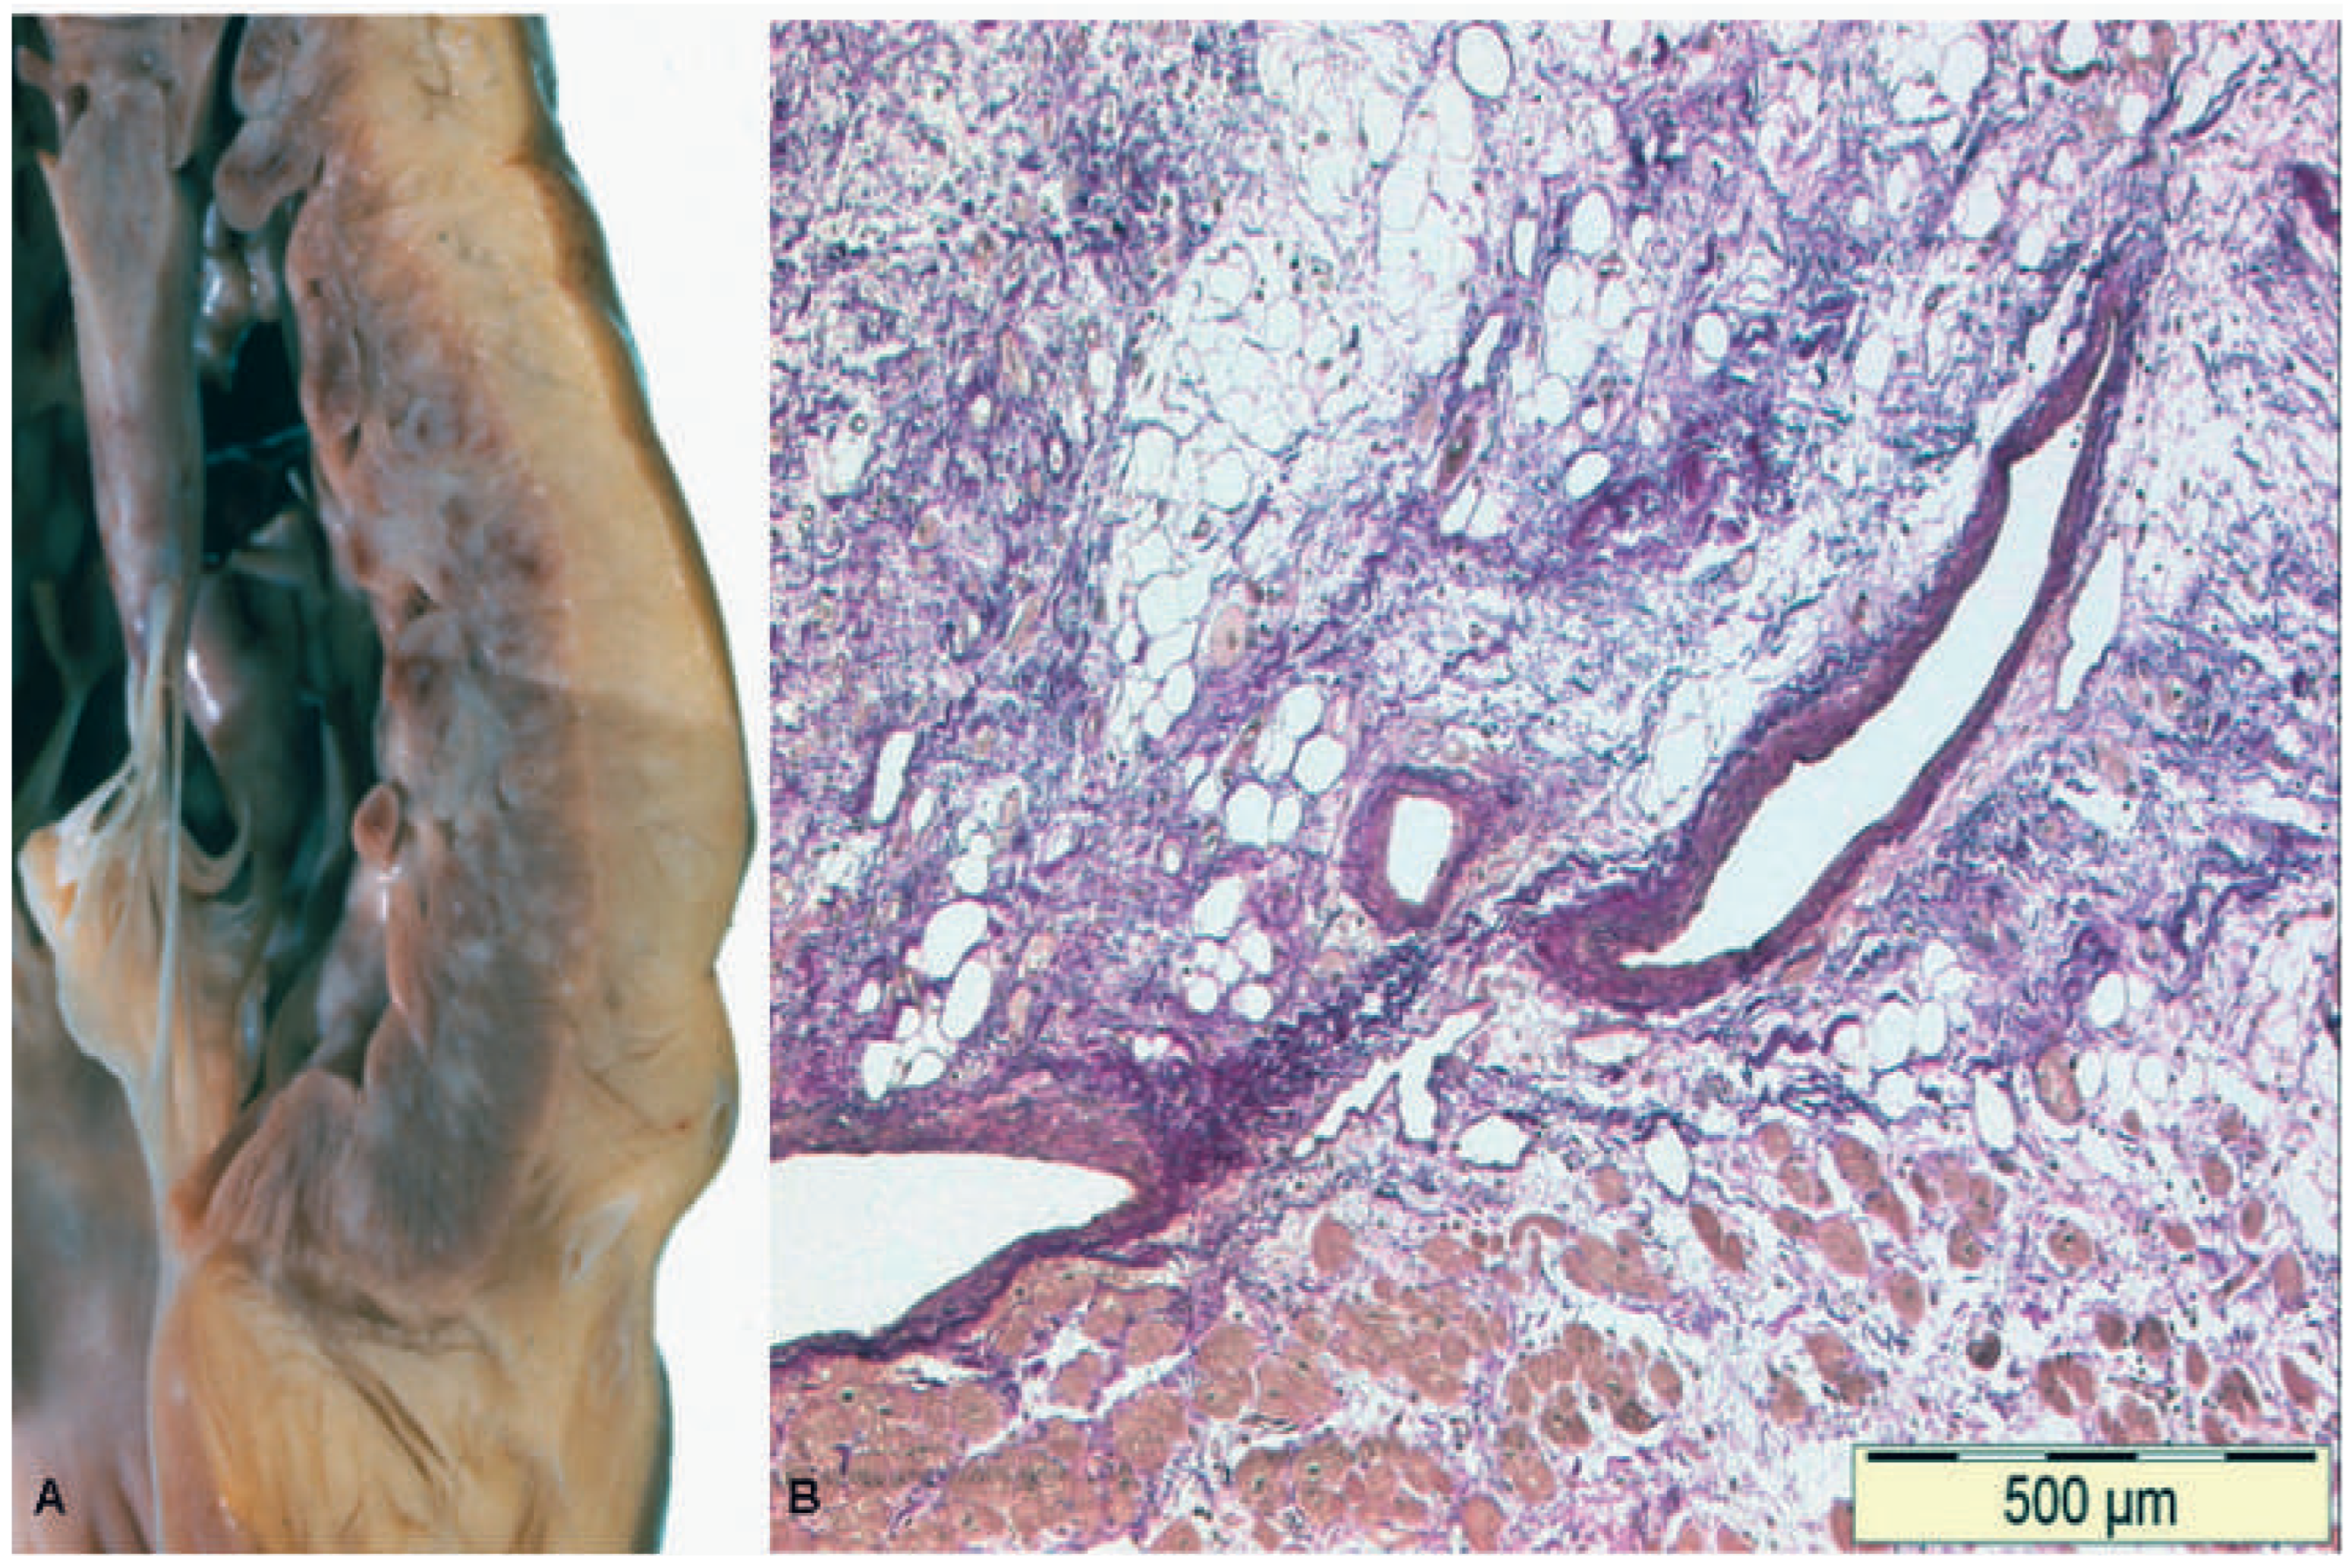

Pathologie und Histopathologie